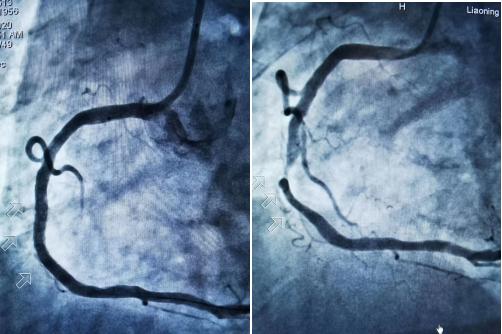

近日,沈阳市苏家屯区中医医院成功开展了辽宁省首例"心脑联合支架"手术。患者因突发左侧肢体无力,以急性脑梗死入院。脑血管造影右颈内动脉95%重度狭窄,住院期间心绞痛发作,冠脉造影右冠状动脉90%狭窄。经神经内外科、神经介入、心内科联合会诊与协作,同台完成心脑联合支架,术后患者病情稳定,健康出院。